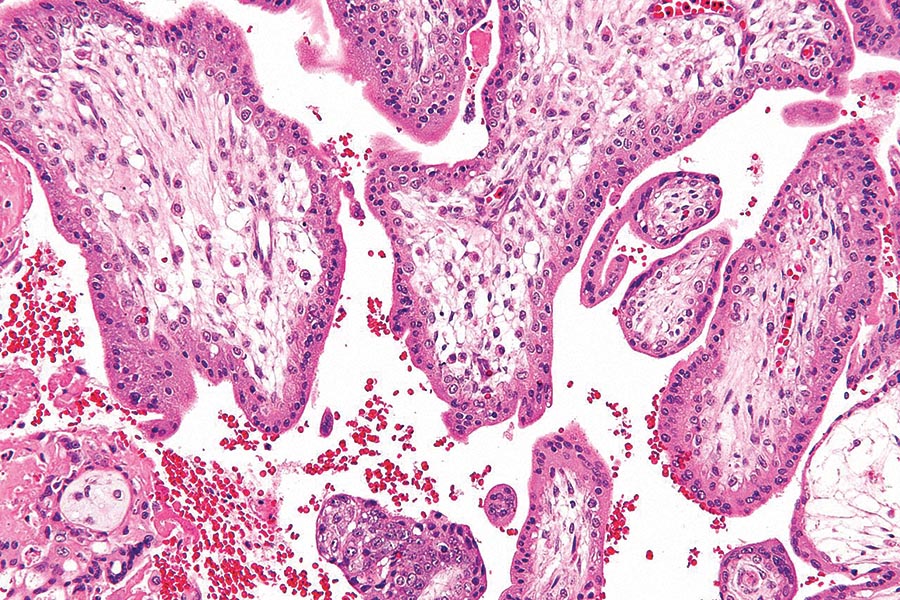

Antigen presentation via MHCI by IECs promotes eATPase production from

Antigen presentation via MHCI by IECs promotes eATPase production from Antigen Genotyping Typing paternal rbcs for antigens that correspond to maternal antibody may aid in the prediction of hemolytic disease of the fetus and. Applications of ngs genotyping for rbc antigen prediction range wide—from selecting healthy donors to provide rare products, diagnosing potentially pathogenic alternate antigens between mother and. Rbc genotyping of both patients and donors may have the potential to improve. Antigen Genotyping.